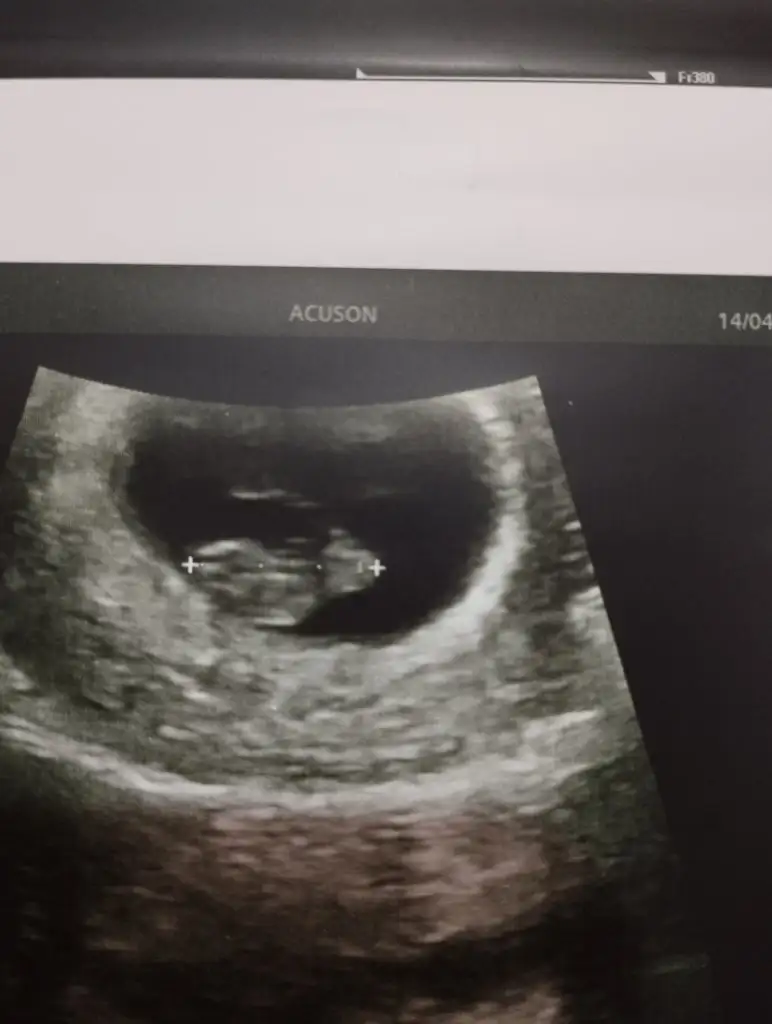

Ay canım bana da baksana 8 haftalık:)Ramziye göre erkek canımsen ne hissediyorsun

Bana da bakar mısınız :) 8 haftalık100 de 100 erkek diyebilirim nubu dik saglicakla alirsin kucagina